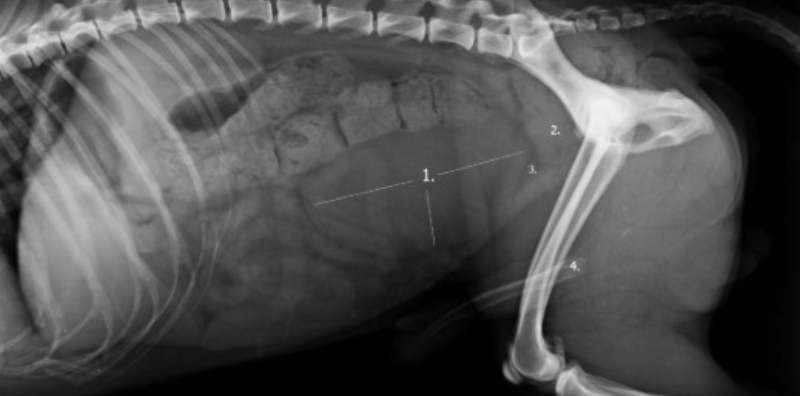

- Radiografía abdominal: muestra la posición de la próstata, vejiga y colon.